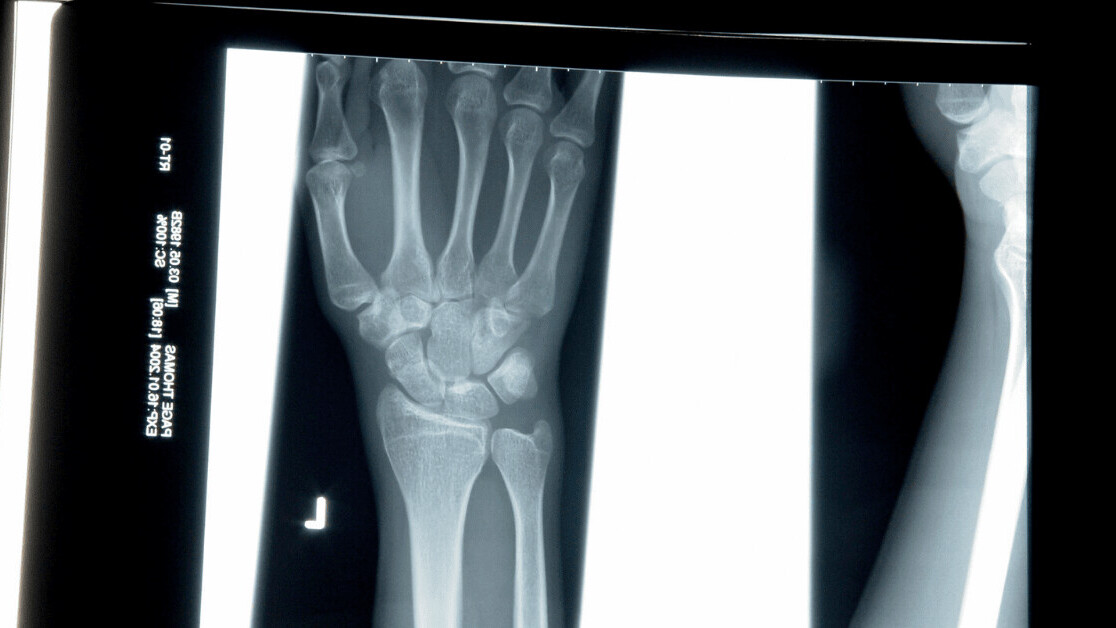

AI’s ability to analyze X-rays, MRIs, and other scans has led it to be hyped up as the future of medical imaging. But patients remain reluctant to use it, as they believe only humans can understand their unique needs.

Many of the studies claiming AI outperforms doctors when interpreting medical images are poor quality and “arguably exaggerated,” according to new research.

The researchers warn that overhyping the power of these systems could lead to “inappropriate care” that poses a risk to “millions of people.”